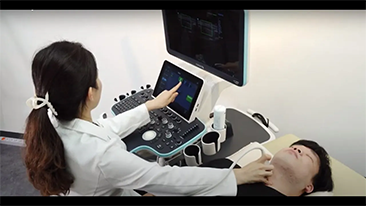

Aparaty ultrasonograficzne z serii Resona, dzi?ki szerokiej gamie za pomoc? wszechstronnych sond do r√≥?nych zastosowaŇĄ i wydajnych narz?dzi do zastosowaŇĄ klinicznych, pomagaj? U?ytkownikom stawia? dok?adniejsz? i efektywniejsz? diagnoz? oraz ocenia? wyniki.

Produkty do obrazowania ogólnego